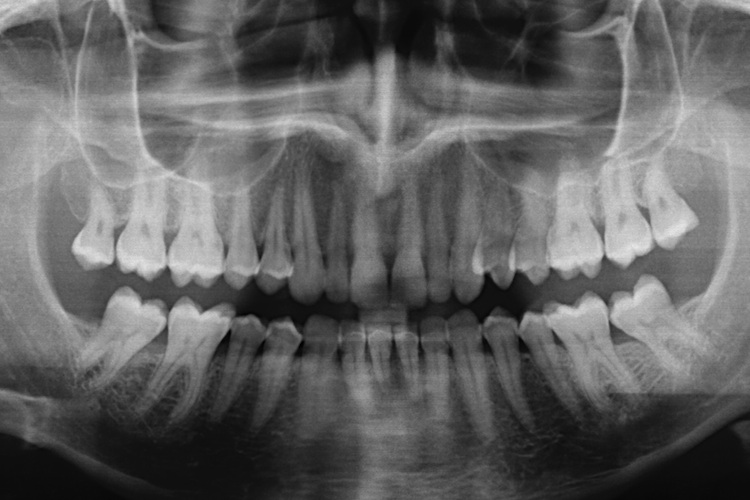

In a video produced by the International Academy of Oral Medicine and Toxicology, an extracted tooth displayed against a phosphorescent screen clearly shows streams of vapor issuing forth. According to the IAOMT, the vapor is being released in amounts 1,000 times higher than the EPA limit for the air we breathe.

Animal studies have shown that mercury fillings cause accumulations of the heavy metal in the jaw, stomach, liver and kidneys - and can spread to every organ in the body. Researchers also found decreases in kidney function - and noted, alarmingly, that mercury migrates to the placenta and fetus as well.

Harold Loe, former director of the National Institute of Dental Research, reports that using mercury requires removing large amounts of healthy tooth substance along with the diseased areas, resulting in a weakened tooth. The tooth may eventually break off, necessitating a crown - which also may break down, leading to costly repairs and, eventually, total failure and extraction.